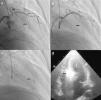

ProcedureThe procedure begins with coronary angiography in order to identify the target vessel, usually the first septal branch to the basal septum, in which systolic milking is visible. The target septal branch may arise from a diagonal, the circumflex, or even the right coronary artery, although the latter was not observed in our population. Following assessment of the coronary anatomy, including ease of access to and caliber of the target vessel, the material to be used in the procedure can be selected. In our center we generally use 6F Judkins and EBU guiding catheters, BMW® or Pilot 50® guidewires (Abbott Vascular, Santa Clara, CA, USA) and Apex Flex® over‐the‐wire balloon catheters (Boston Scientific, Natick, MA, USA). A femoral approach is preferred for greater stability during coronary catheterization. When significant coronary lesions are detected with indication for revascularization, we consider that this should be performed first and ASA postponed pending reassessment of symptoms. In one of our patients the origin of the target septal branch was close to a lesion in the anterior descending artery and stenting would have compromised subsequent access, and so it was decided to perform ASA first and then to treat the lesion in the same procedure (Figures 1 and 2).

Procedure: (a) angiography, right oblique cranial view of the left coronary artery, showing the target vessel; (b) selective catheterization of the target vessel and placement of balloon catheter; (c) selective angiography of the target vessel, showing injection of contrast through the lumen of the balloon catheter; (d) transthoracic echocardiography, 4‐chamber view, showing hyperechogenic basal septum after injection of contrast.

Change in the target vessel after contrast injection: (a) selective catheterization of the second septal branch; (b) selective catheterization of the first septal branch; (c) opacification of the right side of the septum after injection of contrast in the second septal branch; (d) opacification of the appropriate region of the septum (below the anterior leaflet of the mitral valve), following contrast injection in the first septal branch.